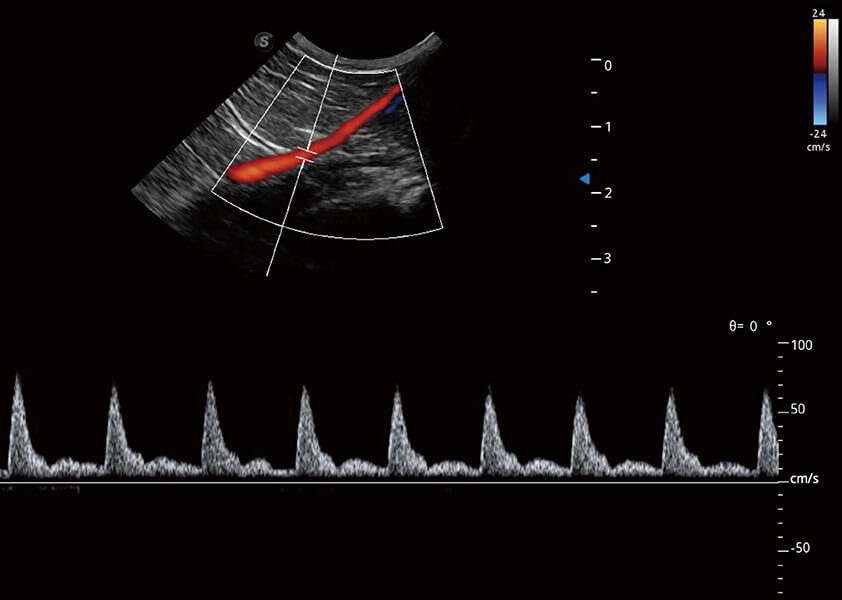

ProPet 60 作为一款高端台式动物超声设备,为动物医生的日常诊断提供了一系列贴合动物临床需求、解决临床实际问题的高级成像功能。凭借全系列高清探头,满足医生对腹部、心脏、生殖、浅表、肌骨等成像的所有需求,切实帮助您提升检查效率,提高诊断信心。

动物是人类最亲密的朋友和最值得信赖的伙伴。狗万官方网站也一直致力于探索动物专用的超声影像解决方案。 全新推出的ProPet系列,是狗万官方网站在动物超声影像智能化、专业化、精准化的一次跨越式革新。动物不能用言语来表述自己的不适,通过超声影像,ProPet系列搭建了动物医生与不同物种沟通的“桥梁”,为动物医生注入了“治愈之力”。